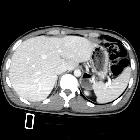

CT/MRI

A well defined saccular collection of fluid or gas that demonstrates communication with the gastric cavity (fills with iodinated oral contrast on CT).

In cross-sectional studies gastric diverticula can mimic a left adrenal mass. In fluoroscopic studies, they may mimic a gastric ulcer.